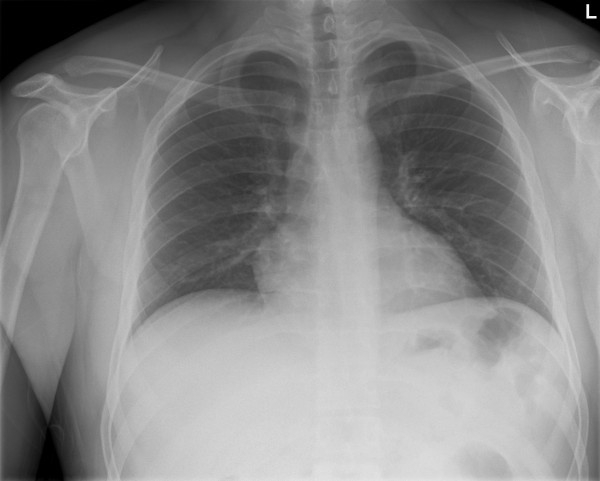

CLASSIFICATION CRITERIA FOR THORACIC AORTIC PATHOLOGY Etiology—Blunt, penetrating Time from injury Clinicopathologic manifestations—Aneurysm, dissection, rupture, emboli be important in traumatic aortic injury, dissection, or even ... Read Content

Reporting Standards For thoracic Endovascular aortic Repair ...